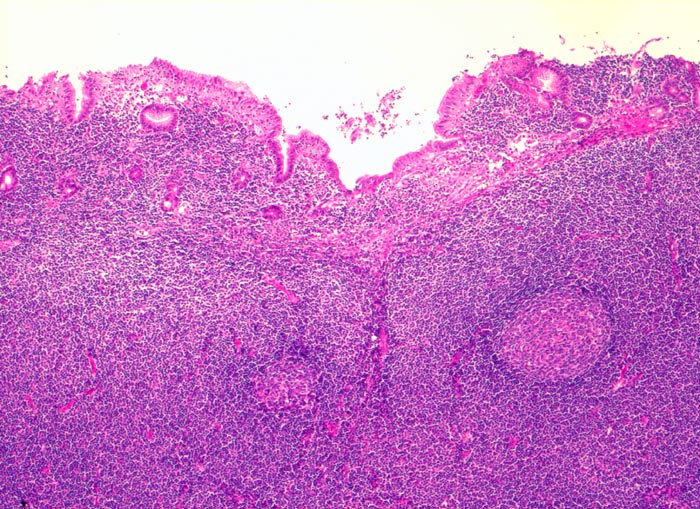

extranodales Marginalzonenlymphom vom MALT-Typ

Magenantrum

Ausbreitung der Tumorzellen in der Marginalzone um und zwischen reaktiven Sekundärfollikeln. Infiltration von Mukosa und Submukosa.

73 jährige Patientin mit chronischer Helikobakter-Gastritis. Magenbefall ohne Lymphknotenbefall.

Oft multifokales Tumorwachstum (Gefahr der falsch negativen Diagnose wegen Trefferfehler bei Biopsie).